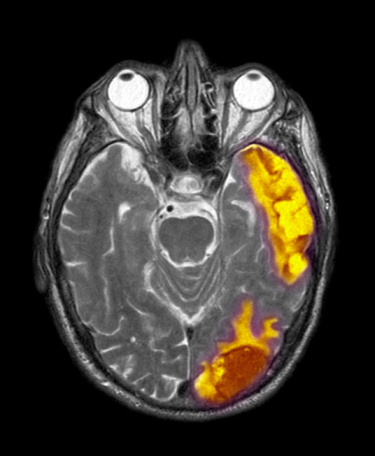

脑肿瘤分为原发性和继发性两大类,高危年龄贯穿20―50岁,因此即使年纪轻轻,也很有可能中招。所幸,还是有一些信号能提醒人们尽早发现它。